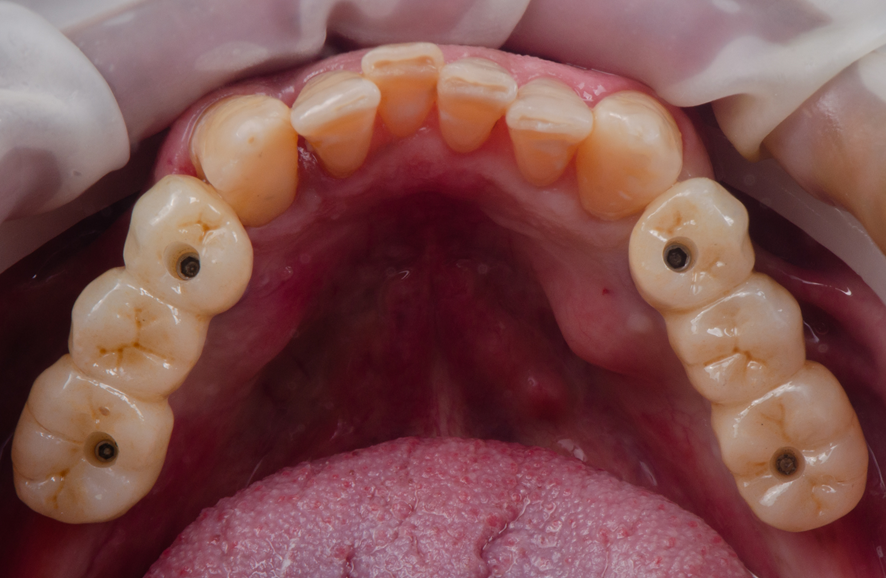

Dessa forma, este relato de caso visa explorar a aplicação prática da reabilitação oral total, em maxila e em mandíbula. Foi realizada a combinação entre prótese protocolo superior e a instalação de implantes e prótese implantossuportada de zircônia no arco inferior.

Por fim, o tratamento finalizou com a carga precoce dos implantes que culminam na instalação dos pônticos de zircônia sobre os implantes.